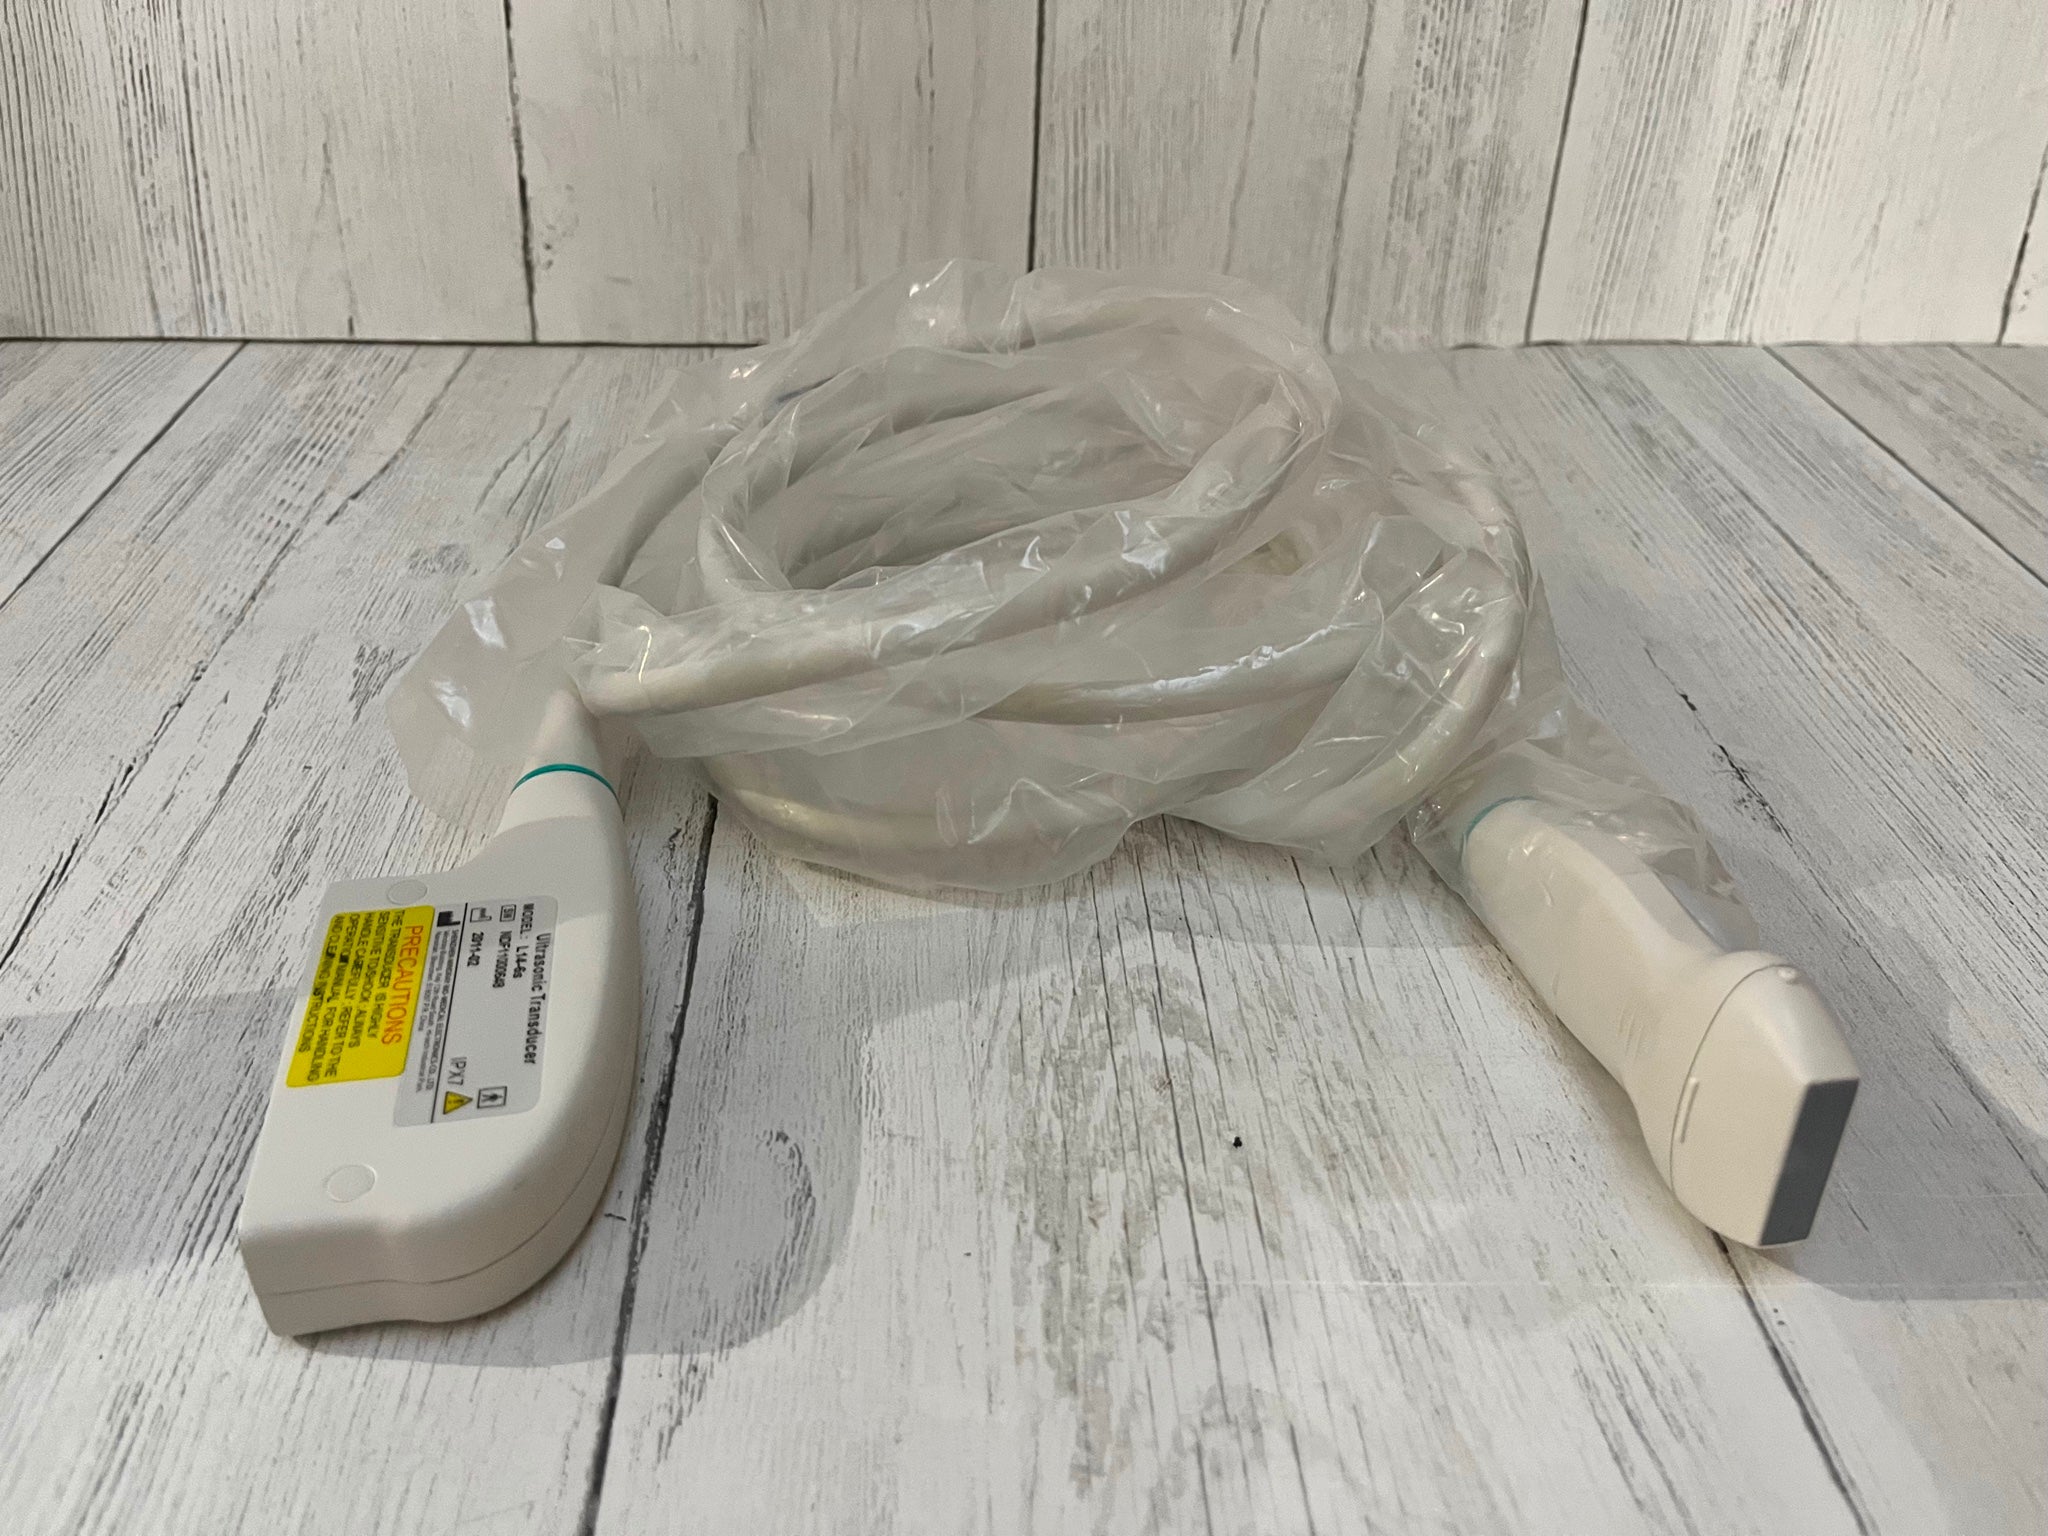

Probe Function: 3.5MHZ convex, abdominal organs

Probe 2: 7.5MHZ Transvaginal probe:gynecologic examination